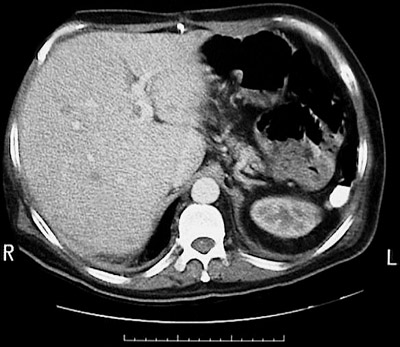

Click on the abscesses in the CT scan of liver above:

This CT scan of the abdomen in transverse view demonstrates multiple small lucent lesions representing abscesses from septicemia. The spleen is absent.